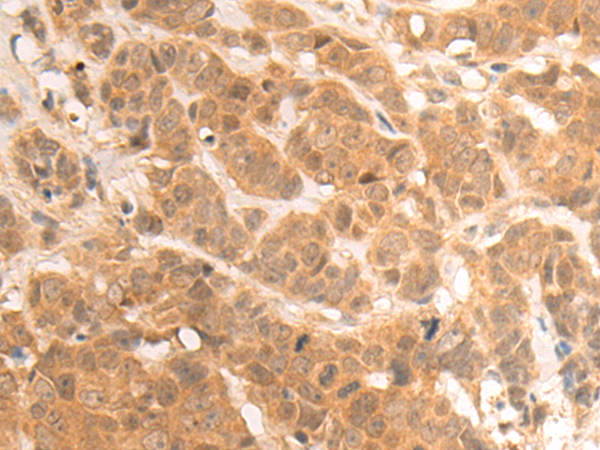

分类: 科研抗体货号: P08938别名: UCH-L3应用: WB,IHC反应种属: Human, Mouse, Rat